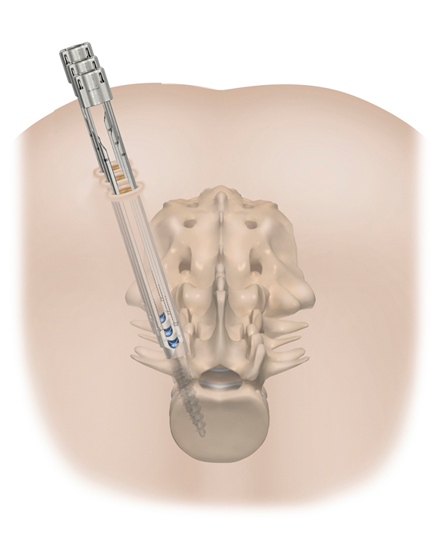

低侵襲経椎間孔的椎体間固定術 MIS-TLIF (エムアイエスティーリフ)

適応となる疾患:腰部脊柱管狭窄症、腰椎変性すべり症、腰椎分離すべり症など

従来の腰椎の後方除圧固定術は、背部に約10~15cm程度の切開を加え手術を行っておりましたが、当院では、皮膚切開を最小限に抑え(通常は約4~5cm程度の創)神経除圧と椎間板切除、人工骨の充填を行います。その後、約2cmの皮膚切開を別に2カ所ほど加えて、レントゲンを見ながら金属スクリューを安全に刺入します。この手術の利点は、筋肉の損傷を最小限にして、出血量低減、術後疼痛の軽減、早期離床、早期退院、早期社会復帰を可能とすることです。手術は2時間から3時間ぐらいで、翌日から起立、歩行が許可されます。入院期間は通常14日間程度になります。